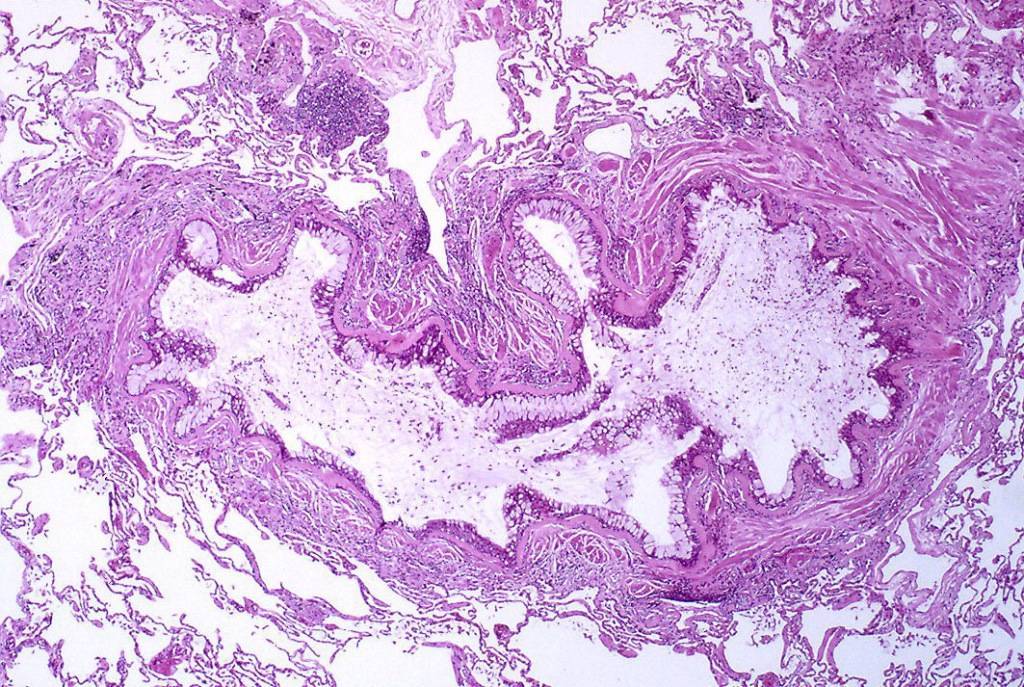

由黏液状的渗出物、杯状细胞化生和上皮基底膜导致的细支气管内腔阻塞在哮喘病人体内增厚。

随着显微镜和新染色技术的逐渐采用,细胞及其成分可以被更清晰地观察。病理学研究发现了一些支持哮喘发作时肺部出现炎症和黏液阻塞的证据。法国著名神经病学家夏科(Jean Martin Charcot)描述了一名患支气管炎的女性痰液中的特殊晶体,德国临床医生莱登(Ernst Victor von Leyden)进一步阐述了它的来源和性质,认为这些晶体可能是支气管痉挛的原因(这种晶体后来被命名为Charcot-Leyden晶体)。几年后,另一位德国医生柯什曼(Heinrich Curschmann),描述了哮喘患者痰液中的螺旋结构(即Curschmann螺旋体),并表明螺旋和晶体都是在较小气道中形成的黏液栓。随后,在哮喘患者的痰液和血液中鉴定出嗜酸性粒细胞(一种白细胞)。Charcot-Leyden晶体和嗜酸性粒细胞之间存在明显的相关性,证实了炎症渗出物在支气管哮喘中发挥关键作用的推测。医学工作者开始坚信:晶体、螺旋结构形成的黏液栓等炎性渗出物在支气管哮喘中发挥了关键作用。19世纪末,支气管痉挛、黏膜炎症两种哮喘理论的支持者间关系持续紧张,许多专业人士开始有了中间立场,认为痉挛、炎症在哮喘患者身上是并行、共存的过程。